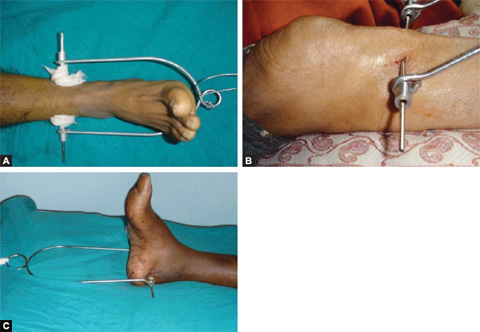

Skeletal traction (Figs. 1.33 and 1.34): It is more definitive form of traction. It is applied by a pin (Steinmann or Denham) through bone and Bohler stirrup. It is used for reducing or maintaining the reduction of a fracture.

Figs. 1.34A to C: Common orthopedic tractions: (A) lower tibial traction; (B) upper tibial traction and (C) calcaneal traction.

Usual sites of skeletal traction are upper third tibia, distal third tibia, supracondylar femur, and the calcaneum in fractures of the lower limb. Olecronon, second and third metacarpals are usual sites in upper limb for passage of pins for skeletal traction.

Complication: Pin site infections, distraction at fracture site, skin necrosis at entry site, damage to the epiphyseal plate in children and rarely osteomyelitis are the few complications of skeletal traction.